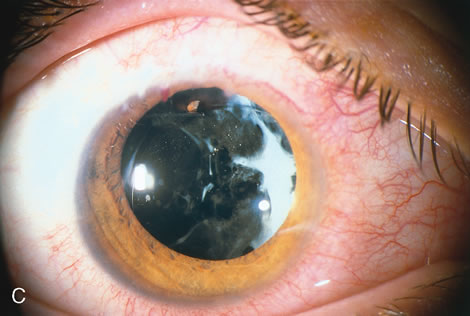

When the vitreous suction-cutting devices became available, they were quickly employed to remove cataracts in children. In addition to providing control of aspiration pressure and control of the flow of irrigation solutions, they also added the ability to remove some or all of the posterior lens capsule, even when the capsule had a thick fibrovascular stalk associated with persistent hyperplastic primary vitreous (PHPV) or a thick capsular plaque (Fig. 2). These fine-tip suction-cutting instruments provided sufficient control of the anterior chamber depth, thus permitting the surgeon to precisely open the posterior capsule and, if necessary, safely remove vitreous from the anterior chamber. Keech and co-workers,12 in a contemporaneous surgical series, showed that having the ability to remove the posterior lens capsule and perform an anterior vitrectomy reduced the need for secondary procedures from 75%, if the capsule was left intact, to 11% after capsulectomy and anterior vitrectomy. They found that when a large section of the posterior lens capsule was removed, it provided a lasting optical opening and reduced the requirement for additional surgery.

As techniques evolved, concerns were raised about the wisdom of removing a portion of the anterior vitreous with the capsulectomy. Occasional reports postulated that cystoid macular edema may occur with these techniques, but the actual risk of developing cystoid macular edema and the long-term results of an anterior vitrectomy on the eye of a child (and in particular on the retina) remain unknown.13 This relatively new capability of safely removing a portion of the lens capsule, or even the entire posterior lens capsule, gave rise to controversy. If only a small portion of the posterior capsule was removed, opacification could recur. Experience showed that the lens would develop pearls at the edge of the posterior capsulotomy, and these lens epithelial cells could migrate across a scaffold created by the anterior vitreous face. If the entire posterior lens capsule was removed, recurrence of posterior capsule opacification would usually not occur, but the barrier effect of the posterior lens capsule between the anterior chamber and vitreous was lost.

With the incremental acceptance of use of the IOL as the principal method of rehabilitating children's eyes, the issue of the formation of secondary membranes has become more complicated. Authors have advocated opening the posterior lens capsule at the time of the cataract surgery either by using vitrectors, or by performing a posterior lens capsule capsulorhexis, with or without prolapsing the lens optic through the posterior capsular opening.18–24 These measures however, do not ensure that the visual axis will not become opacified.25–27.